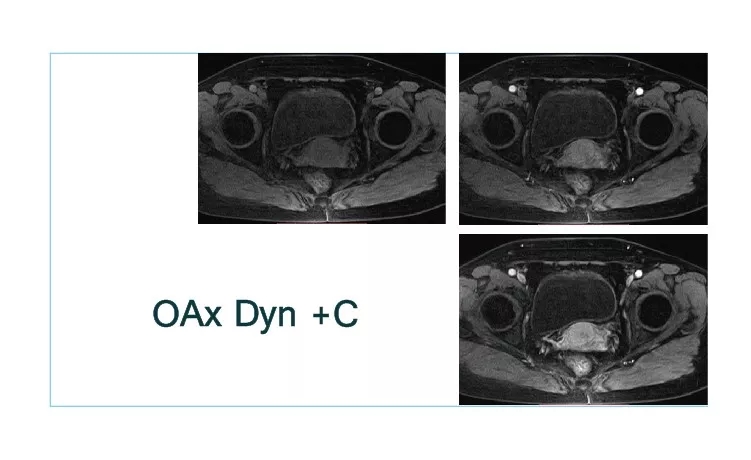

【朗润影像档案】20180930磁共振影像病例结果讨论